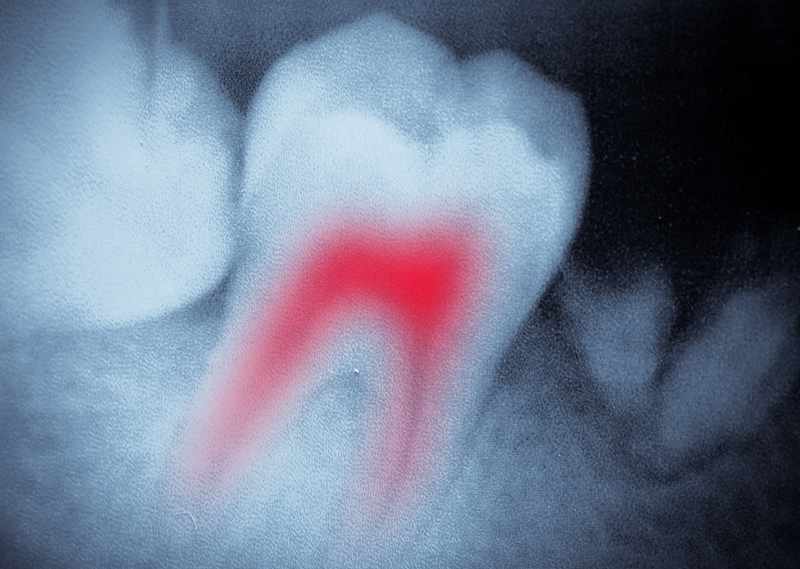

The internal nerves and pulp of teeth can become infected as a result of fracture or serious decay. This can be extremely painful and lead to inflammation and swelling.

This involves gently removing the soft tissue from within the tooth and cleaning the internal canals. These are then filled with a replacement material known as gutta-percha.

Finally the tooth is sealed to protect it from any further damage.